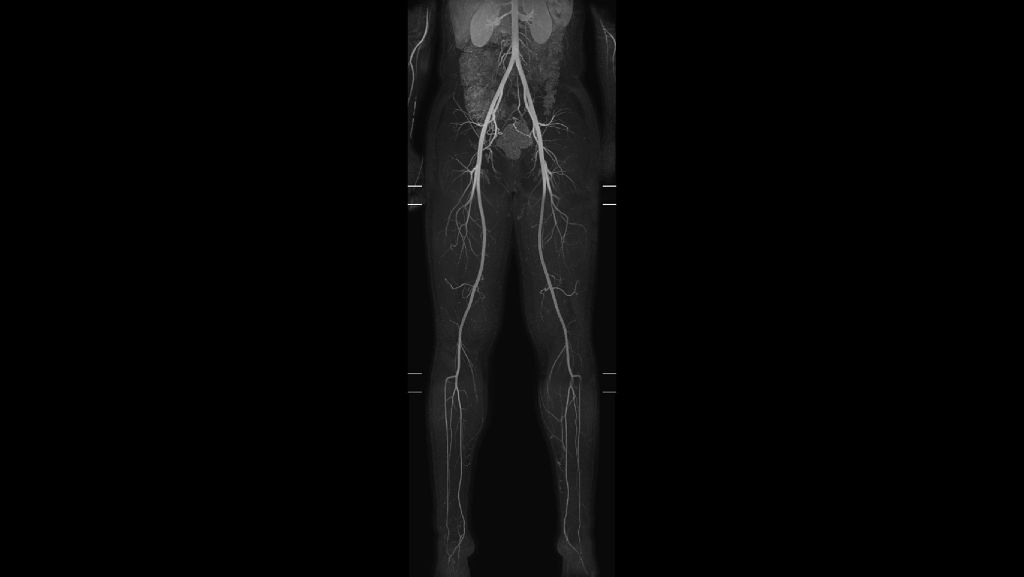

mDIXON XD MultiStation allows you to perform peripheral MR Angiography with improved vessel-to-background contrast in only one single pass¹. You will be able to perform your peripheral MR Angiography acquisitions without the use of a subtraction mask, eliminating artifacts that could arise from misalignment, due to patient motion, between the pre and post contrast scan. Enjoy fast, robust peripheral MR Angiography.